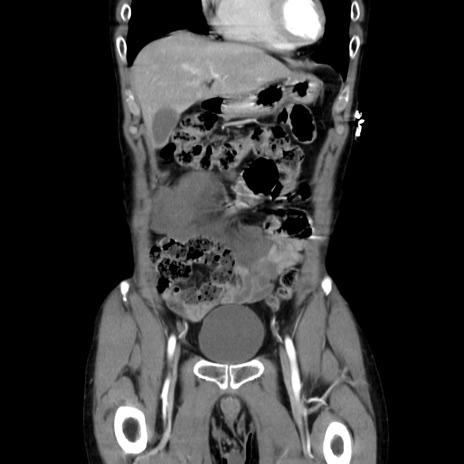

症例37(冠状断像)

【症例】40歳代 男性

【主訴】腹痛

【現病歴】4時間ほど前に電車に乗車中に臍部上より腹痛出現。徐々に増悪し起立困難となり、救急外来受診。生ものは数日食べていない。今朝お雑煮を食べた。

【身体所見】BT 36.8℃、BP 117/84mmHg、HR 91/min、SpO2 97%、苦悶様、腹部:臍上部広範囲圧痛あり、反跳痛±

【データ】WBC 8100、CRP 0.03